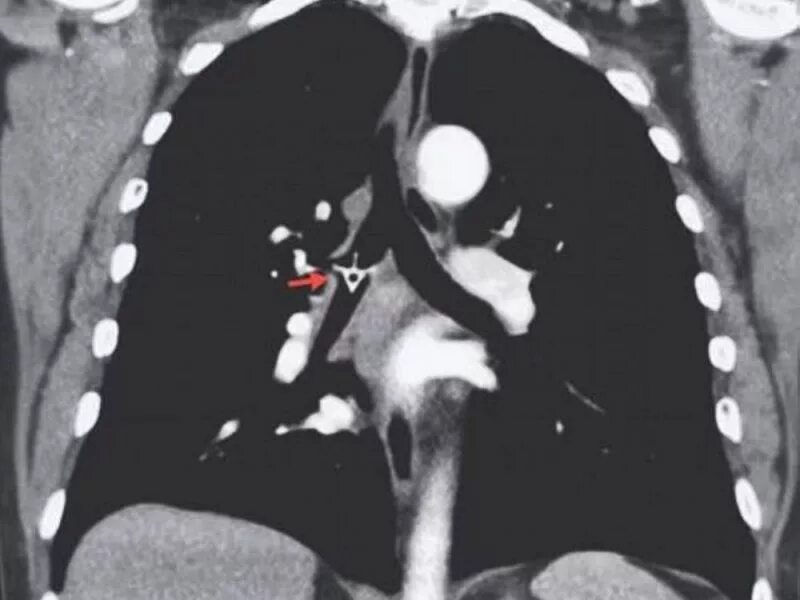

Как достать косточку из горла